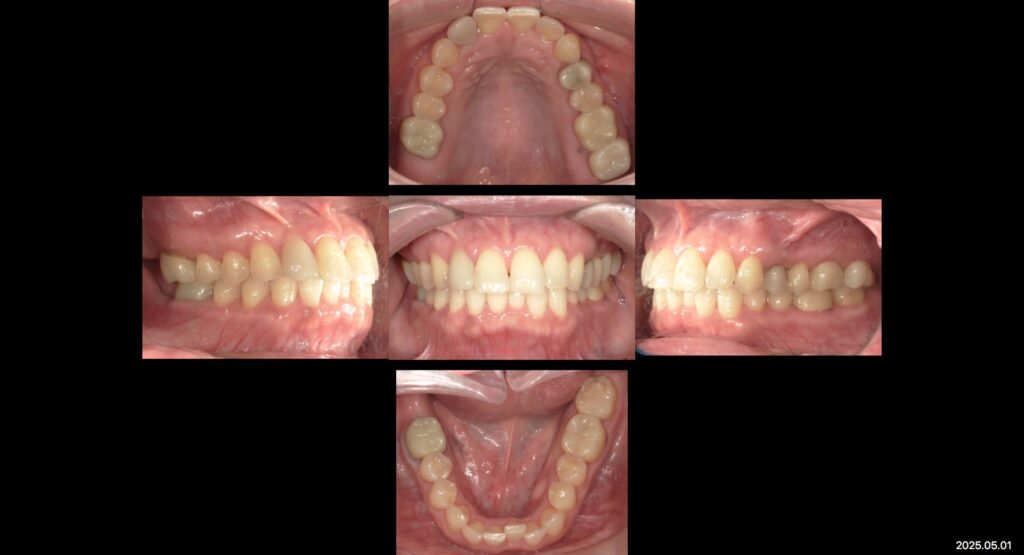

下:治療後口腔内写真

今回は補綴治療を終えた患者様の症例写真です✨

噛み合わせ、見た目を目的に補綴物のやりかえなど全顎的に根本治療を行いました。

補綴治療後ホワイトニングも行い審美的にもきれいに治療を終えました。

現在は、メンテナンスに通っていただきながら経過観察を追っています。